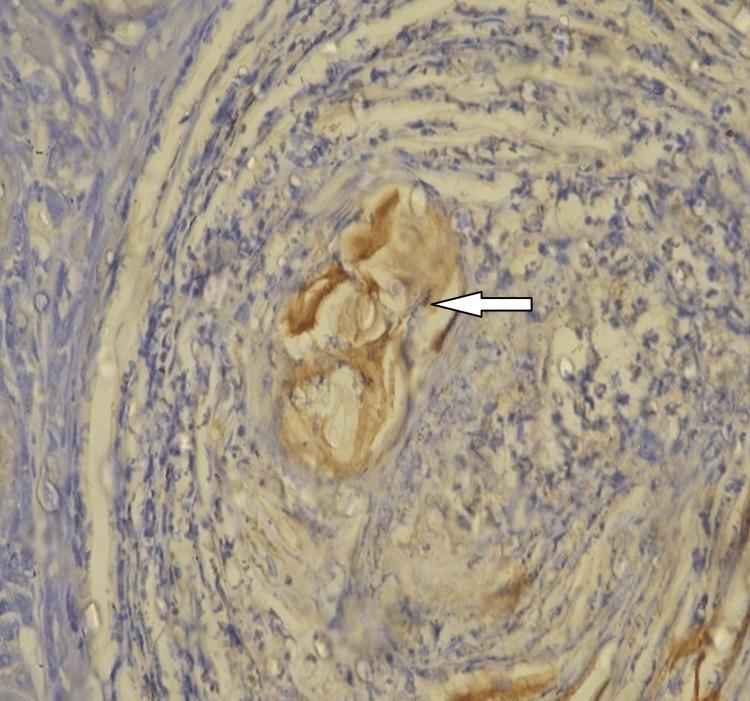

In the group treated with DMBA, the mean quantity of iNOS positive foci per section was roughly 12.2+/-4.7. The DMBA-treated pouch keratinocytes showed both nuclear and cytoplasmic stainings. Neither the mineral oil-treated nor the untreated pouches (n=10) showed any signs of iNOS activity.

在DMBA处理组中,每切片iNOS阳性灶的平均数量约为12.2±4.7。经DMBA处理的颊囊角质形成细胞显示出细胞核和细胞质染色。经矿物油处理的颊囊和未处理的颊囊(n = 10)均未显示出任何iNOS活性迹象。